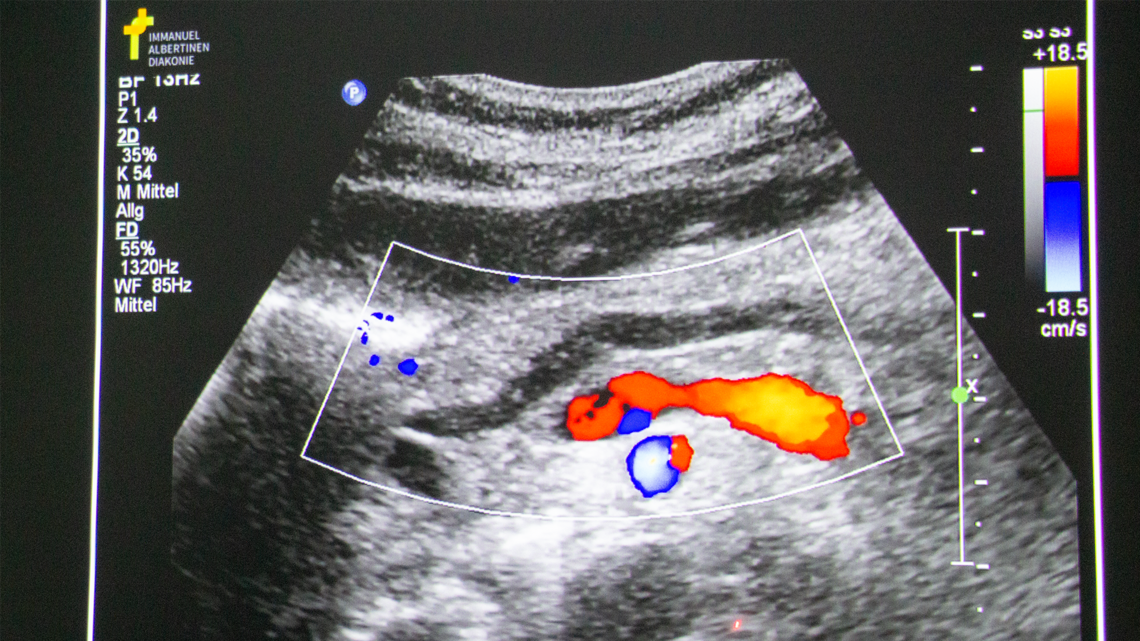

Durch Ultraschall, auch Sonografie oder Sonogramm genannt, wird über die Nutzung von Schallwellen ein bewegtes Bild des Körperinneren erzeugt. Dieses ist maßgeblich bei der Untersuchung von Organen, Muskeln, Gelenken oder Blutgefäßen sowie der Suche nach möglichen Erkrankungen und Veränderungen des Gewebes.

Da braucht es ein scharfes Auge und viel Erfahrung: „Als Faustregel gilt: Wenn es krank ist, dann ist es besser zu erkennen“, wie Michel André Bott, Chefarzt der Inneren Medizin, erläutert. Doch wie sieht das im Ultraschall aus? Das wird anhand von realen, lehrreichen Fällen aus dem klinischen Alltag deutlich. Die werden eifrig in der Gruppe begutachtet – schon nach kurzer Zeit erkennen die Teilnehmenden Auffälligkeiten am Zwerchfell bei einem Patienten, der gestürzt ist. „Das deutet auf einen Hämatothorax hin“, bemerkt eine Teilnehmerin. Korrekt, es hat sich also Blut zwischen Lunge und Brustwand angesammelt, der Brustkorb wurde durch den Sturz verletzt. Bei einem weiteren Patienten wird mittels Ultraschall ein lebensgefährliches Pankreaskarzinom gefunden, ein bösartiger Tumor in der Bauchspeicheldrüse.

Die genaue Analyse der Ultraschallbilder ist eine Herausforderung für das ungeübte Auge: „Es ist nicht einfach, alles zuordnen zu können und das grau vom grau zu unterscheiden – man braucht viele Wiederholungen“, berichtet ein Student mit Blick auf die Grauabstufungen, die unterschiedliche Gewebe- und Strukturarten zeigen.